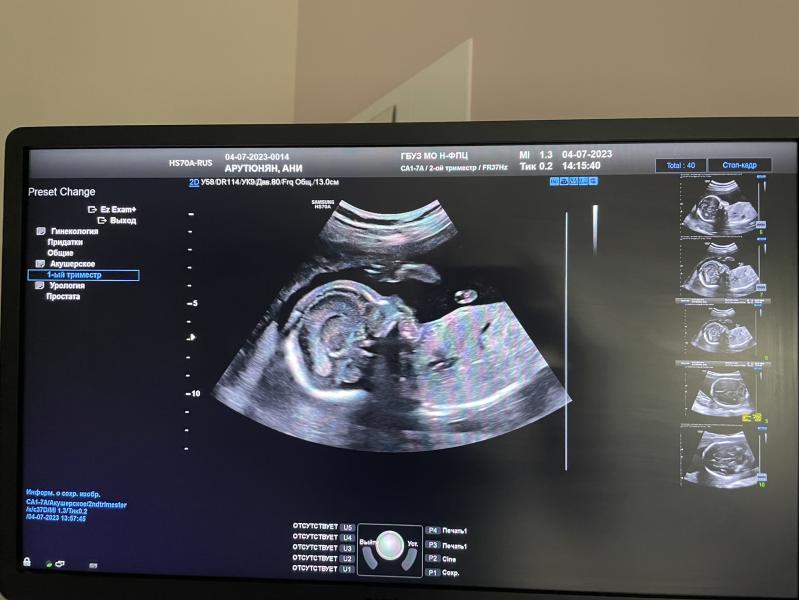

Сегодня были на втором скрининге(20.2недели)🙂 малыш хорошо подрос, а главное здоровый. Вес малыша 390г…Рубец на матке тож отлично 👌